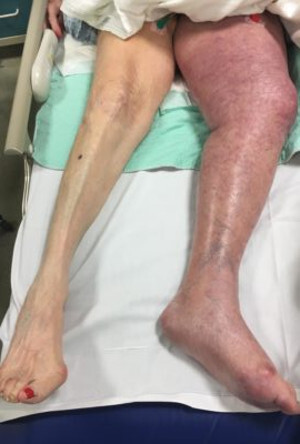

- тромбоз глубоких вен - болезненность по всей ноге или по ходу вен, отек голени, с разницей противоположной стороны больше 3 см, покраснение.

Необходимо проведение дуплексного сканирования вен нижних конечностей.